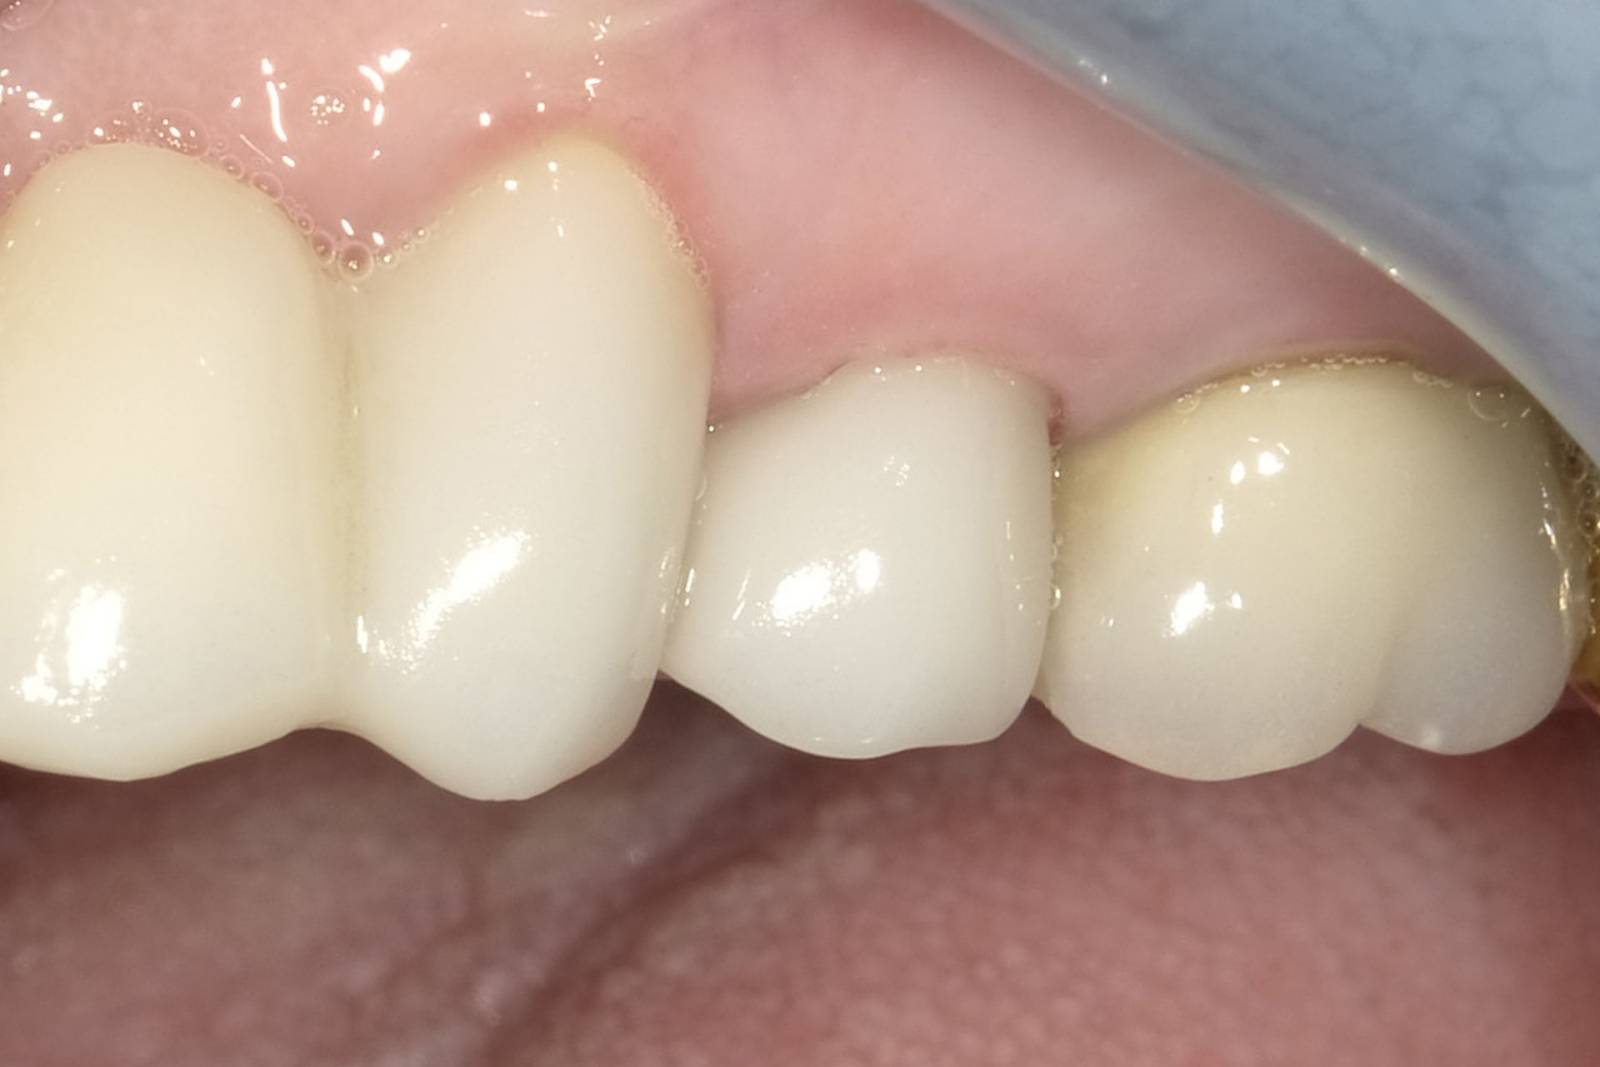

First upper premolar in 90 minutes

Ankylos implant placement and IPS e.max CAD single Crown

Within 90 minutes the final prosthetics after an implant treatment were produced and placed, thanks to the digital chairside workflow with CEREC. The patient was very pleased with that.

Before: Tooth 24 with horizontal root fracture and peripheral infection.

After: Preservation of esthetics and the natural soft tissue contour.

Dr. Carlos Repullo

Sevilla, Spain